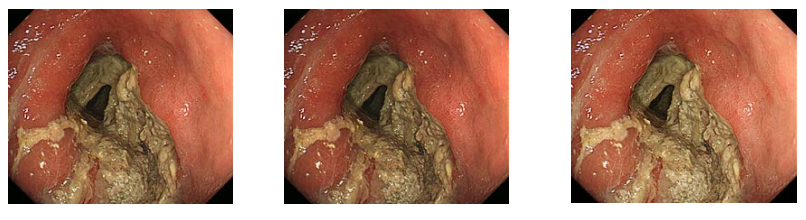

Poniżej zestawiono oceniane obrazy dla porównania.

Rys. 13 Przykładowe obrazy ES (Hybrid Gamma PXL po lewej, GSDF w środku, 2.2 po prawej)